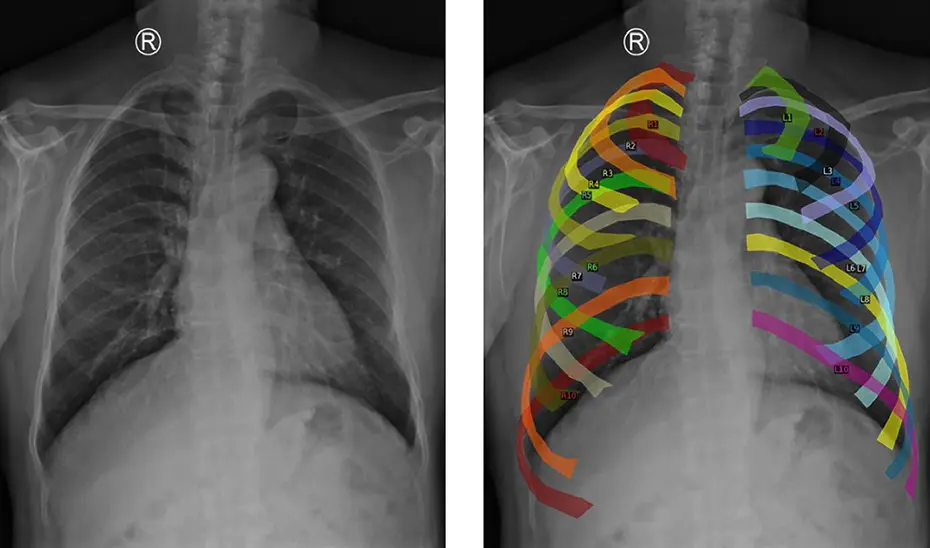

Puntos clave del tórax

Para una mejora en el entrenamiento del modelo, se han empleado datos de distintos centros hospitalarios y una estrategia conocida como aumento de datos, en las que se segmentan las costillas y se alinean puntos clave del tórax para generar nuevas imágenes homogéneas desde una perspectiva anatómica. Con esto, se consigue que sea robusto, incluso ante radiografías de distintos hospitales, de diferente resolución o adquiridas con otro equipamiento. El sistema aprende mejor y funciona de forma más generalizada.